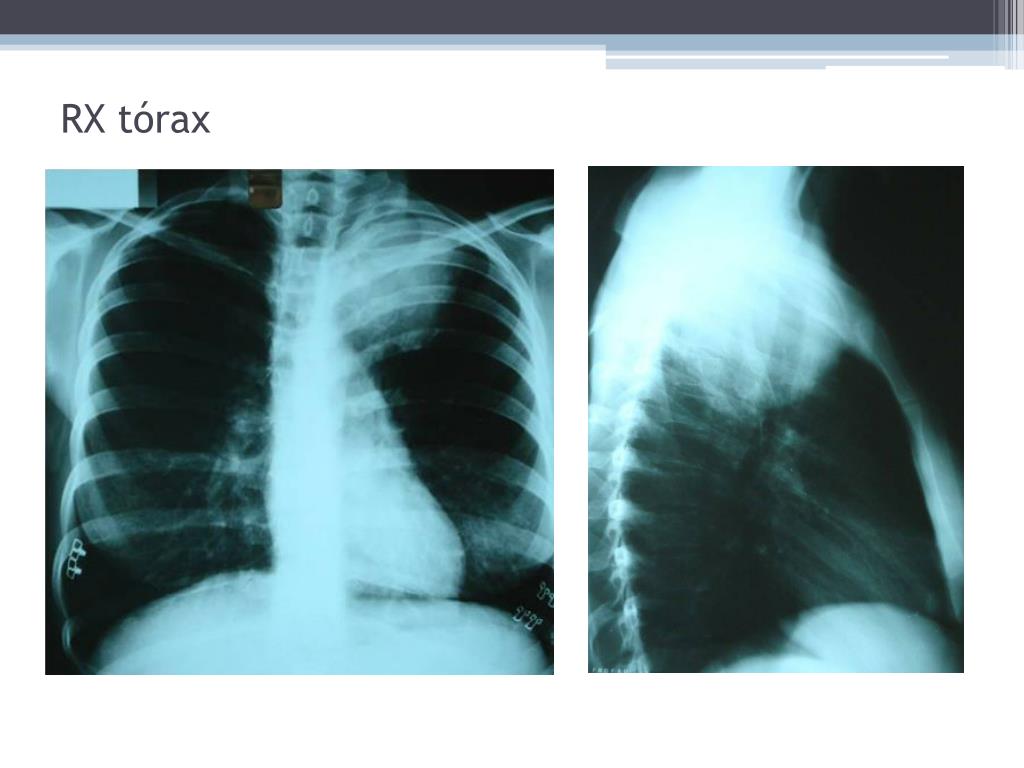

14. RX tórax

21. Síndrome de Pancoast - Diagnóstico • Anamnese e exame físico • RX de tórax demonstra um tumor apical, (em alguns casos, pode ser negativa e o tumor identificado apenas na TAC do tórax. • RNM é útil para melhor avaliação da invasão tumoral através da pleura, do envolvimento do plexo braquial e dos vasos subclávios. • Broncoscopia e citologia são conclusivas em 10 a 20%. • O método diagnóstico mais eficaz é a punção transtorácica percutânea guiada por USG ou TC